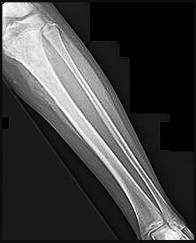

Figures 9a through 9d are the anteroposterior and lateral radiographs, CT scan, and technetium bone scan of a 12-year-old boy who has experienced 7 months of pain in his lower leg. The pain limits his ability to participate in sports and he is having difficulty sleeping. He is afebrile, and laboratory study findings including an erythrocyte sedimentation rate, C-reactive protein, and complete blood count are within normal limits.

The images and clinical history support a diagnosis of osteoid osteoma, which most commonly occurs in adolescence. Although these lesions can be seen in any bone, they are usually located in the femur and tibia. The significant inflammatory response to this tumor is secondary to high levels of prostaglandin production. Characteristic night pain is relieved with nonsteroidal anti-inflammatory drugs (NSAIDs) or by aspirin.

Radiographic images show thickened bone and a small central nidus. Thin-cut CT scan is the imaging of choice to visualize the nidus. A bone scan is associated with uptake but is not specific. Treatment options include expectant management with NSAIDs and observation under the premise that these lesions eventually burn out. Contemporary treatment involves RFA. Historically, these lesions were treated with en bloc resection; however, this technique has largely fallen out of favor because of the high efficacy and comparative low morbidity associated with RFA.

When an osteoid osteoma occurs in the spine, it is located in the posterior elements, and paraspinal pain and scoliosis often are present.